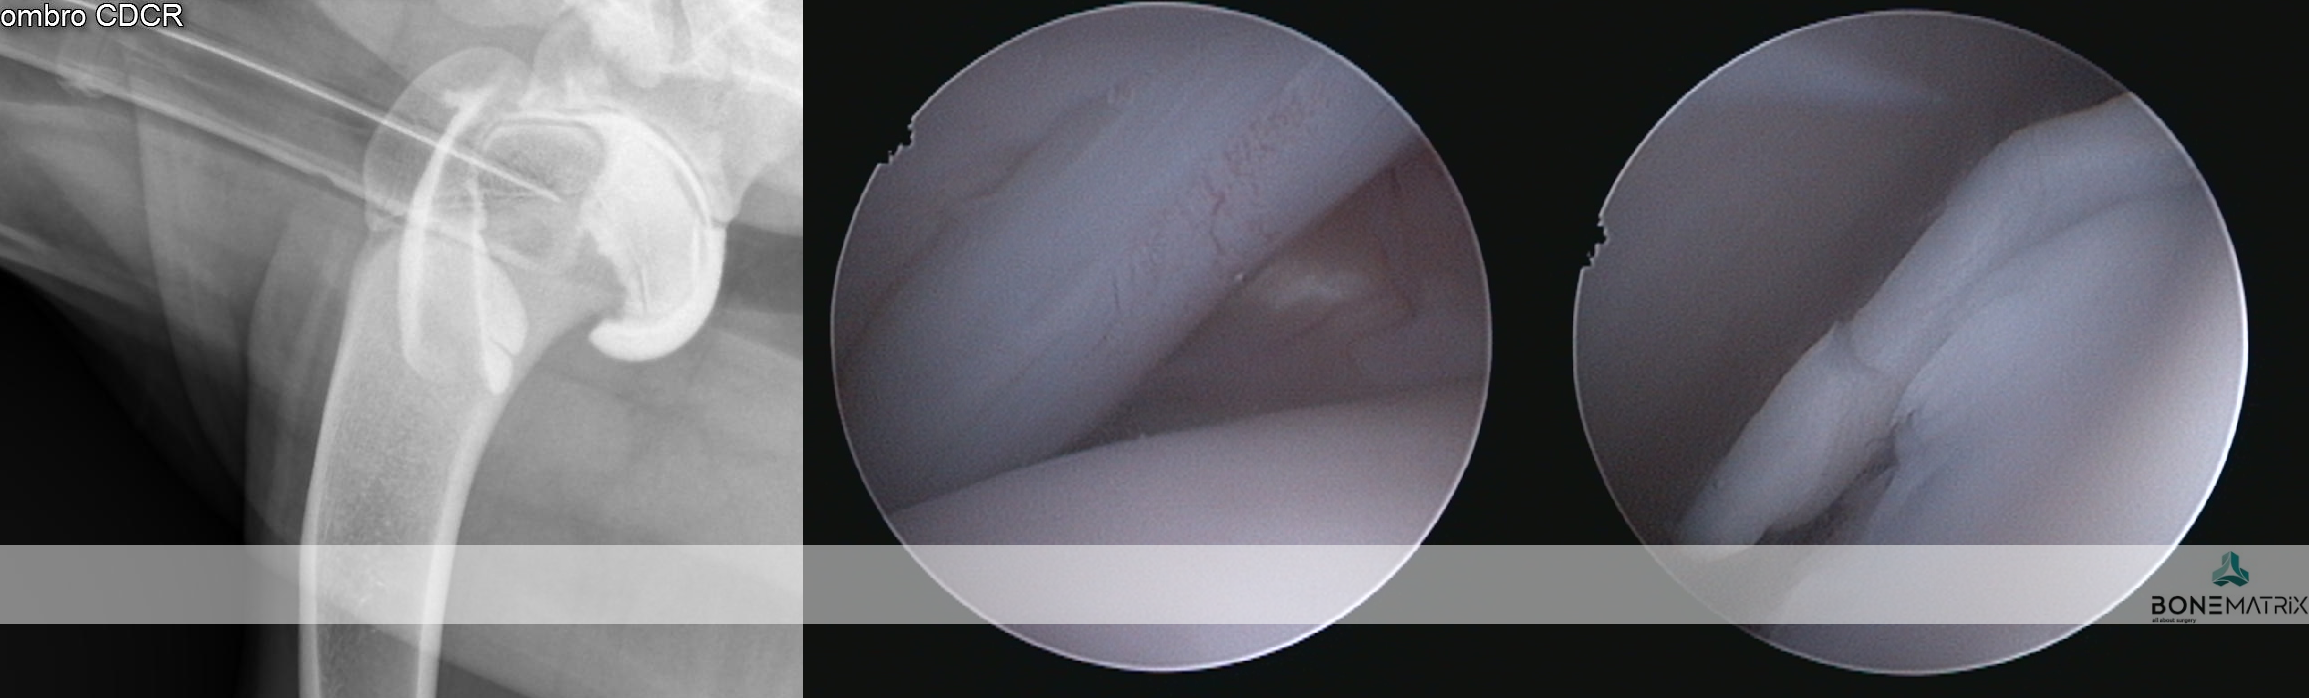

O que é?

A osteocondrite dissecante é uma condição que surge durante o crescimento devido a um distúrbio na diferenciação das células de cartilagem, o que resulta numa falha na ossificação endocondral (processo fundamental do desenvolvimento esquelético do feto e do cachorro em crescimento). Este defeito no crescimento resulta no aparecimento de um defeito ósseo tipicamente apresentado na cabeça do úmero, da qual se destaca um “flap” de cartilagem.

Como é feito o diagnóstico de OCD?

A suspeita surge quando se deteta claudicação, dor e desconforto no ombro, entre os 6 e 10 meses de idade. Alguns pacientes podem passar assintomáticos durante os primeiros anos, e mostrar desconforto numa fase mais avançada da doença e da idade. Após exame ortopédico, o diagnóstico é geralmente confirmado com um estudo radiográfico.

Situações mais subtis podem carecer de confirmação com estudo de TAC ou artrografia (radiografia com contraste articular).

Quais os tratamentos disponíveis para OCD do ombro?

A artroscopia é o tratamento “gold standard” da OCD. Neste procedimento minimamente invasivo, são efetuados pequenos orifícios (2.4mm) através dos quais são introduzidas uma câmara de filmar e instrumentos apropriados. O “flap” articular é removido desta forma, sem necessidade de recorrer a uma abertura cirúrgica da articulação. Este processo de tratamento garante uma recuperação rápida e confortável.

É utilizado Synacart em casos onde a lesão osteocondral é muito extensa e a simples remoção do “flap” pode revelar-se insuficiente. Nestes casos podemos optar por uma técnica de “ressurfacing” que tem como objetivo cobrir o defeito ósseo com um implante Synacart ou um implante especialmente desenhado para o efeito. Estes implantes têm uma porção metálica porosa que integra no osso subcondral e uma superfície de polímero polido que mimetiza a superfície de cartilagem perdida.